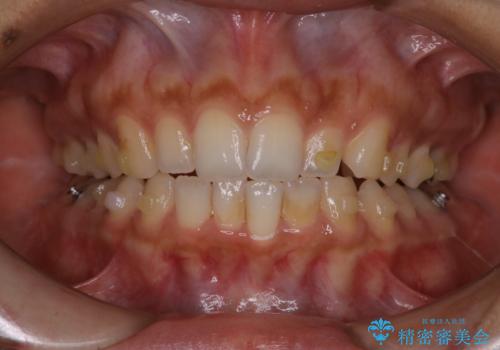

タバコによるヤニをPMTC(歯科医院での専門的クリーニング)で除去。

担当医 歯科衛生士